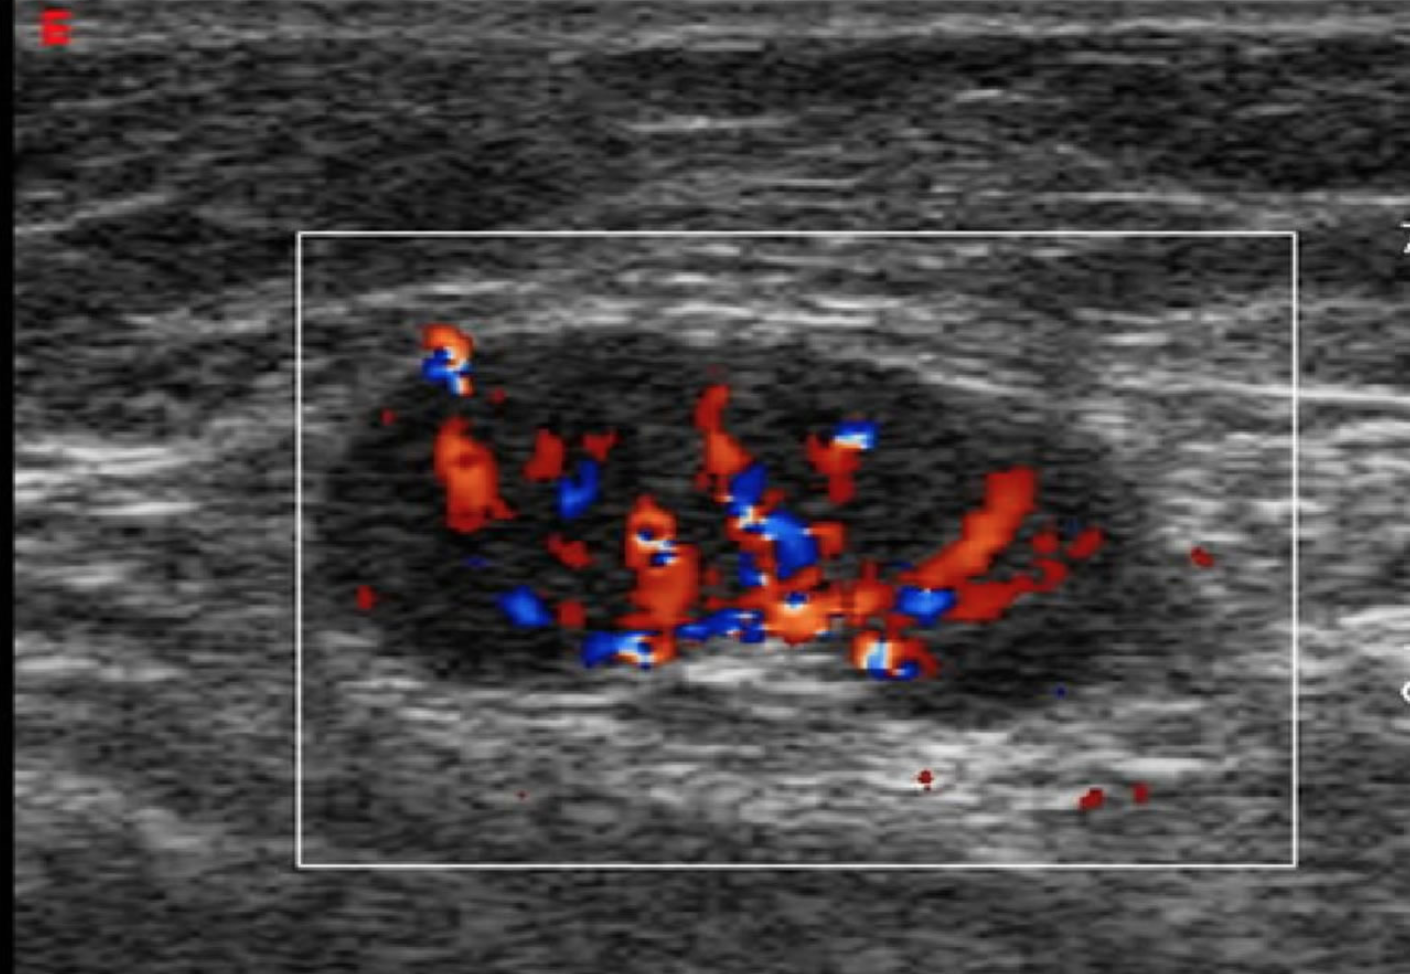

- Color or Power Doppler can be used to distinguish pulsatile flow of arteries vs more laminar flow of veins.

- Lymph nodes will appear as nodular or cystic structures often with internal flow.

- Figure 4. Picture of a lymph node